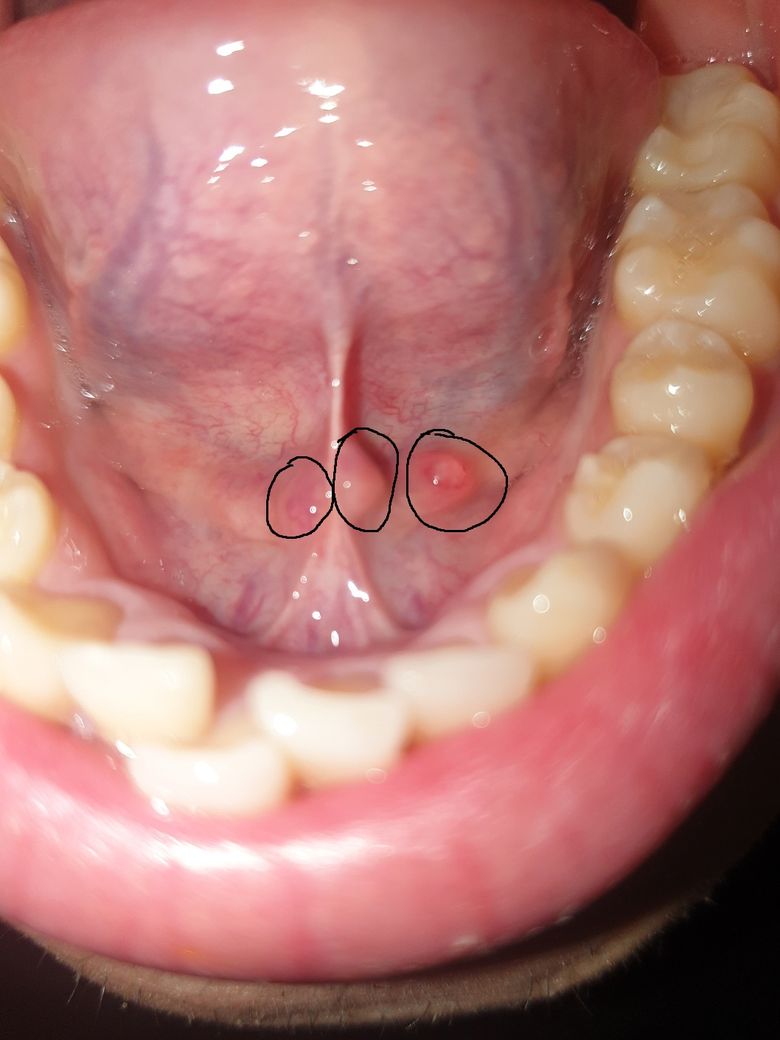

혀 밑에 물집 ? 이 생겼는데 괜찮은 걸까요 ?

혀를 움직일 때 이전과는 다른 이질감이 들어 거울을 보고 확인했더니

혀 밑에(동그라미 친 부분) 물집 같은 게 생겼더군요 ...

• 1번 째 사진

나란히 2개 붙은 동그라미 부분은 정상적으로 침이 나오는 구멍으로 보입니다. 뒷쪽 큰동그라미 부위는 물집이 잡힌 것으로 보이며 주로 상처 때문에 생기는 점액성 수포로 보입니다. 사이즈가 작아 저절로 없어질 가능성이 높아 보입니다. 3-4일 정도 기다려 보시고 저절로 안 없어지면 치과에 가서 흐트리면 됩니다.